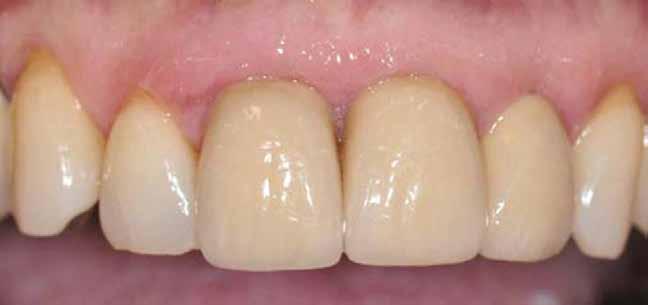

1. a–d. ábra: Műtét előtti állapot mind a négy páciensnél. 1. eset (a). 2. eset (b). 3. eset (c). 4. eset (d).

8. a–b. ábra: Végső röntgenfelvétel az implantátum helyzetéről (a) és a szájon belüli végső szituáció az 1. esetről (b).

9. a–b. ábra: Végső röntgenfelvétel az implantátum helyzetéről (a) és a szájon belüli végső szituáció a 2. esetről (b).

10. a–c. ábra: Végső röntgenfelvétel az implantátum helyzetéről (a) és a szájon belüli végső szituáció a 3. esetről (b és c).

tottuk (az okklúziós koncepciók alapján az implantációs pótlások nem voltak vezető fogak, és csak könnyű érintkezéseket alakítottunk ki, amelyeket artikulációs papírral ellenőriztünk). A páciensek instrukciókat kaptak a megfelelő szájhigiénére vonatkozóan, összpontosítva a fogköz kefékkel történő tisztítására. Végső kontroll röntgenfelvétel készült. A PEEK felépítmény nem radioopák, így az implantátum és a korona közötti távolság könnyen meghatározható a röntgenfelvételen: a felépítmény megfelelően illeszkedik az implantátumban, ha az implantátum válla és a korona alsó széle közötti rés 0,55 mm a röntgenfelvételen (8–11. ábra)

11. a–b. ábra: Végső röntgenfelvétel az implantátum helyzetéről (a) és a szájon belüli végső szituáció a 4. esetről (b).